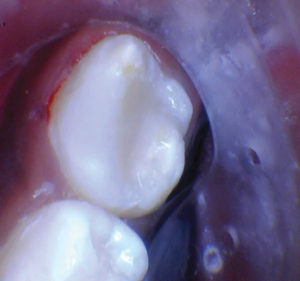

Caso 1

Un paciente de 8 años presentó descomposición de OD en un primer molar primario con síntomas de pulpitis reversible. El diente fue el tratamiento planificado para una restauración de OD con Activa Bioactive Restorative (Pulpdent). Tras la excavación por descomposición, se produjo una exposición pulpar que requirió una pulpotomía terapéutica. Debido a la edad del paciente, me sentí cómodo con una pulpotomía terapéutica con Biodentine (Septodont) seguida de una restauración estética. Si el paciente hubiera tenido entre cuatro y cinco años, me habría restaurado con una corona de acero inoxidable debido a su historial comprobado de longevidad.

Figura 1 Vista preoperatoria del primer molar primario superior. |